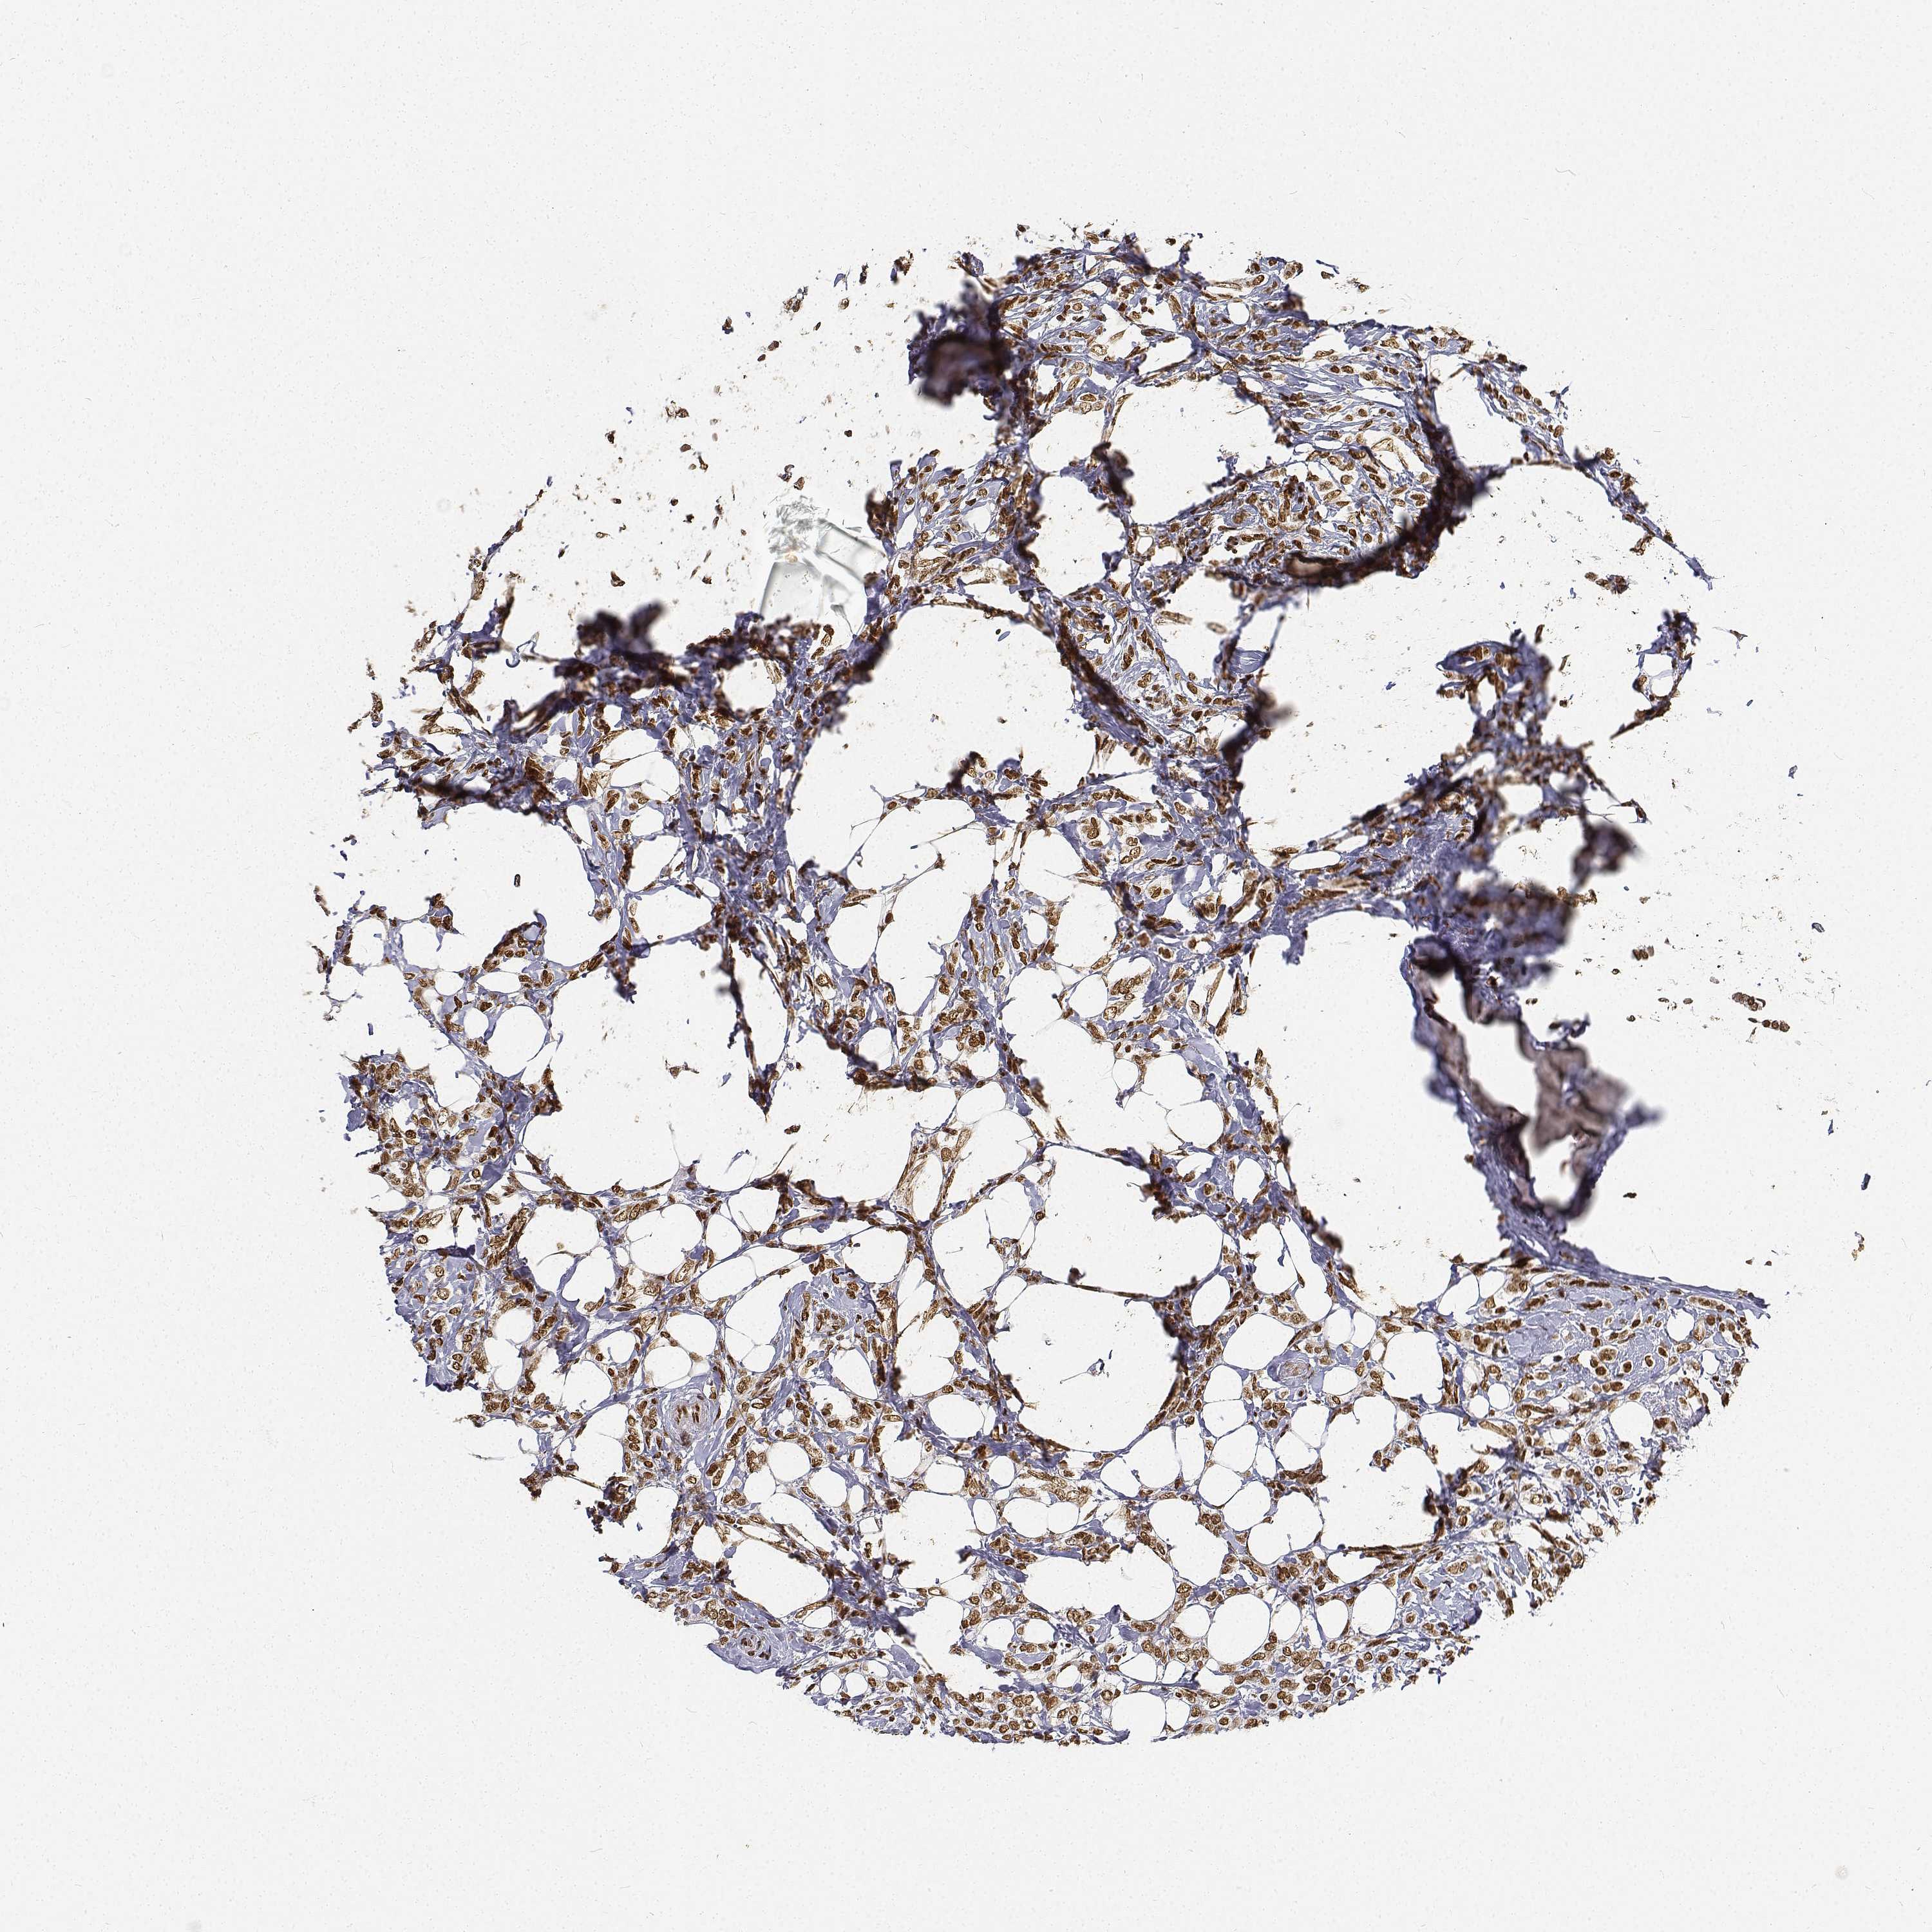

CANCER BREAST CANCER Show tissue menu

BRCA TCGA BRCA VALIDATION PROTEIN EXPRESSION